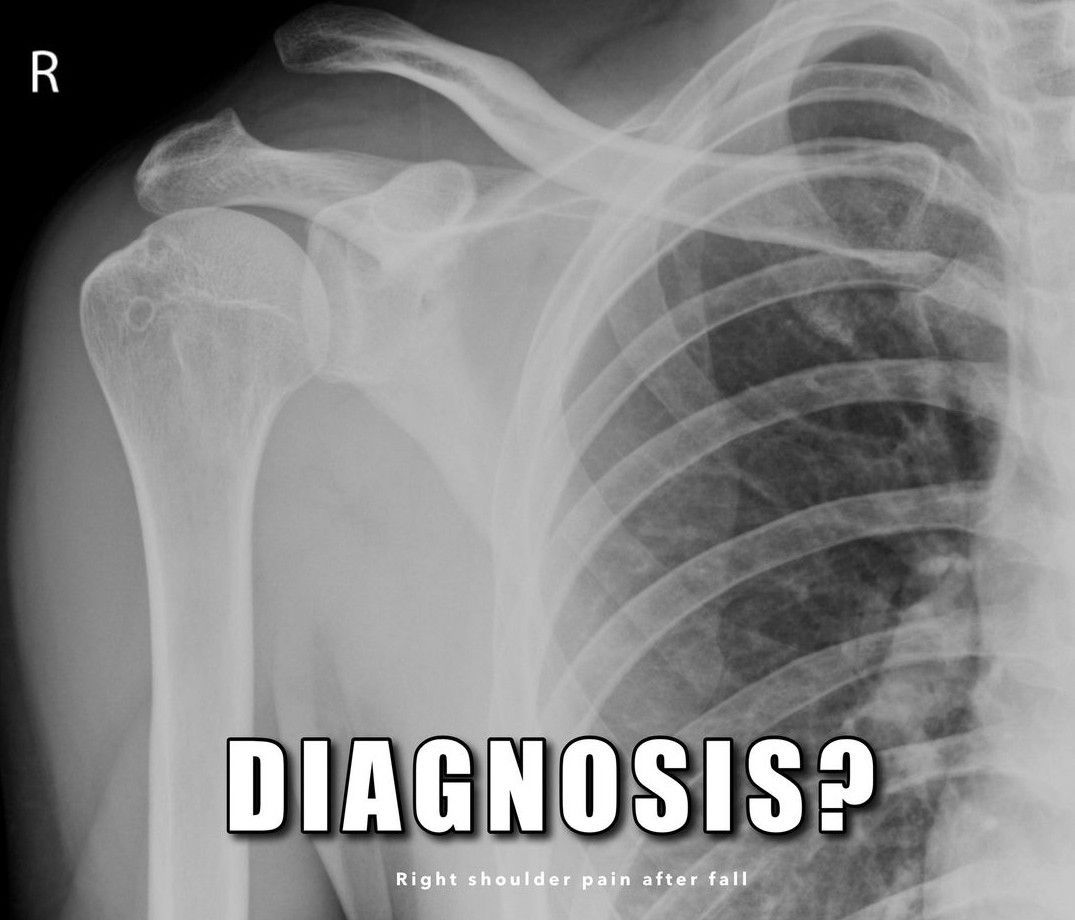

Diagnose It

Diagnose the case with the given radiological presentation.